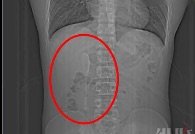

CT 촬영을 해 보니, 길이 약 15㎝인 숟가락 모양의 물체가 찍힌 것이다.

6개월 간의 위장 운동으로 인해 이 스푼은 십이지장 구부(구부러진 지점)와 하행부(아래 쪽으로 내려가는 지점)의 접합부에 정확하게 꽂혀 있었다고 한다.

이 부위는 구멍이 좁고 장벽이 매우 얇아 이물질이 쉽게 박히고, 주의하지 않으면 천공이 발생하기 쉬운 부분이다.